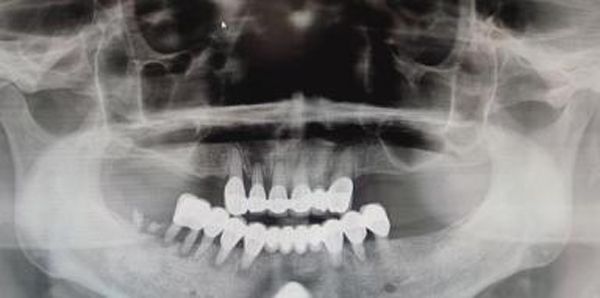

金红主任在对王阿姨进行口腔系统检查和X线辅助诊查后为患者制定了全面的诊疗方案,安抚患者情绪,合理安排时间,无痛化为患者依次拆除原有不良修复体、拔除无法保留牙齿。王阿姨自觉诊治过程舒适,消除了自己治牙及拔牙的恐惧心理,后续待拔牙创愈合良好后将为患者进行义齿修复。